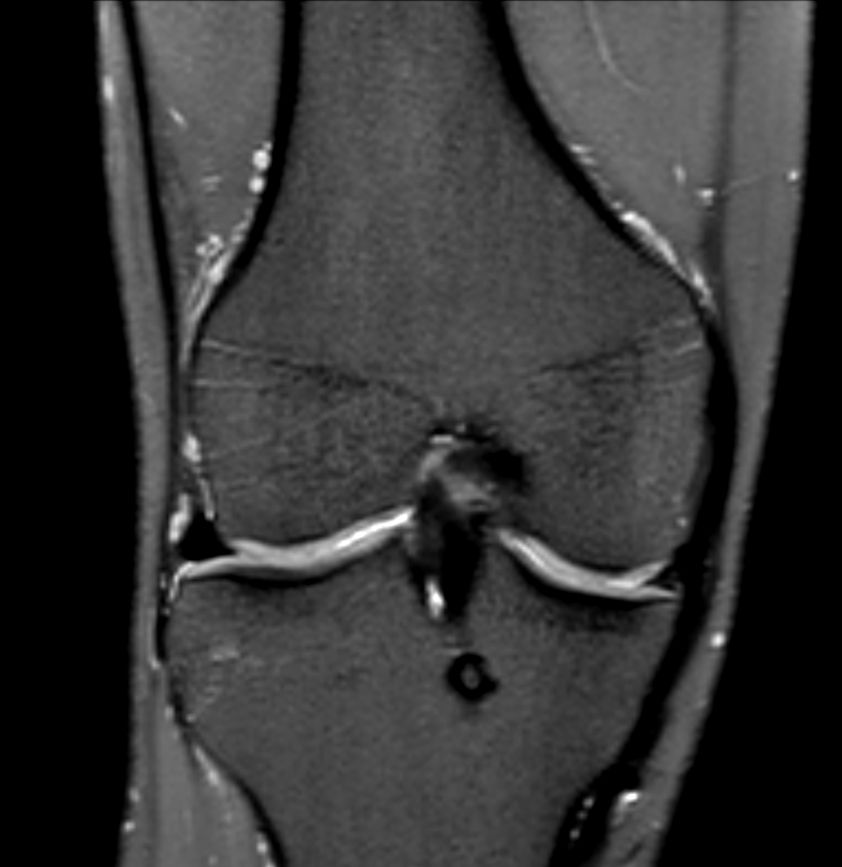

Knee ACL repair

Axial T2w TSE

Coronal T1w TSECompressed SENSE

Sagittal PDw SPAIRCompressed SENSE

Coronal PDw SPAIRCompressed SENSE

Sagittal 3D PDw SPAIRCompressed SENSE

Coronal 3D PDw SPAIR (reformat)Compressed SENSE